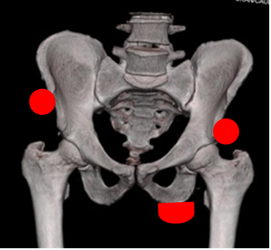

El sitio mas frecuente es la tuberosidad isquiática, donde se originan los tendones de hamstring. De estos, el bíceps femoral es el mas comúnmente lesionado. El siguiente lugar mas frecuentemente lesionado, es la espina iliaca anterior superior, origen del músculo sartorio y el tendón de la fascia lata. A nivel de la sínfisis púbica, se lesionan los músculos aductor mediano, aductor menor y el recto anterior. (15). (Fig 76).

Fig 76. Avulsión.

TAC reconstrucción en 3D. Lugares mas frecuentes de las avulsiones. Tuberosidad isquiática, espina iliaca anterior superior e inferior.